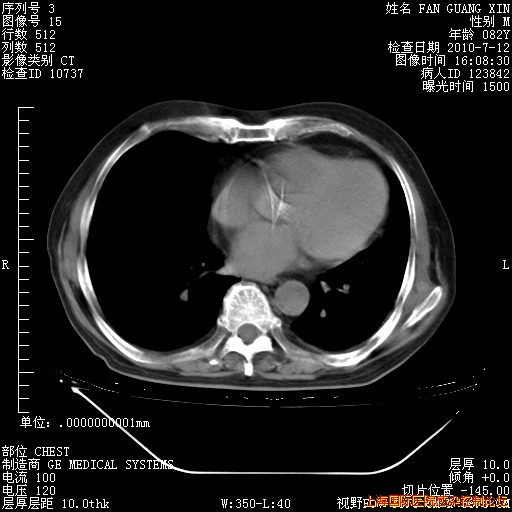

今天CT

整整相隔30天的肺部CT好像有所好转啊。甲强龙减量第3天,需要观察体温。

海管,自昨日你和我通完话后,不知您岳父消化道症状有无缓解?体温怎样?阅读7.12日胸部ct,个人认为目前激素治疗是有效的,甲强龙减量是适宜的。因在抗痨治疗,需密切观察肝功、肾功能和血常规。不过,老年、长期住院和大量使用激素,很担心菌群失调发生